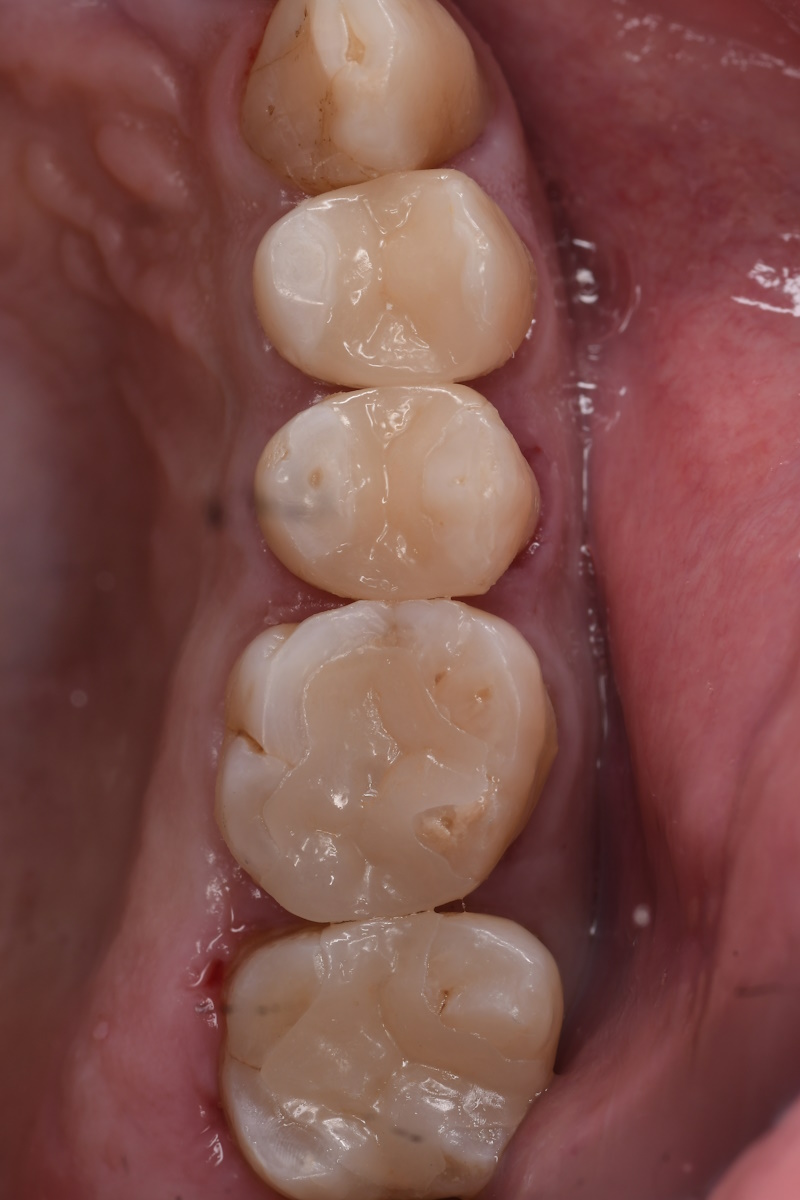

セラミック治療・60代(男性)- 「10年以上前に入れた銀歯をセラミックにやり替えたい」

10年以上前に入れた銀歯をやり替えたいとのご希望で来院されました。

当院にて虫歯治療を行い、その後、セラミックによる修復を実施しました。

治療の際は、接着効率を高めるためにラバーダム防湿を併用し、2回に分けてセットを行いました。

セット後

- 治療内容 セラミック治療(アンレー)

- 施術費用 88000円×4本

- 通院回数 2,3回

- メリット 審美性に優れており、天然歯に近い自然な色や形に仕上がります。金属を使わないため、金属アレルギーの心配がなく、高い適合精度と耐久性によって、美しさと機能を長く維持しやすくなります。

- リスクと副作用 セラミック治療は保険適用外(自由診療)です。強い衝撃や過度な力が加わると、まれに割れることがあります。治療後にしみる症状がみられることがありますが、多くは時間とともに落ち着いていきます。